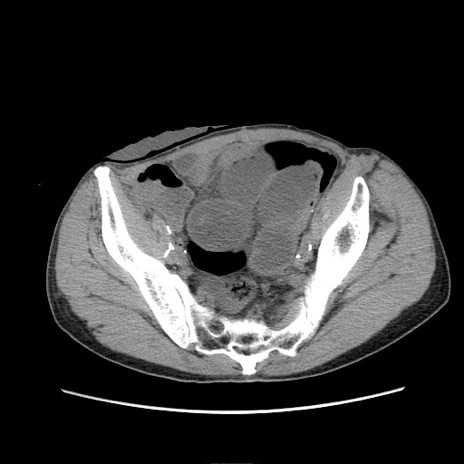

症例11(横断像)

【症例】 60歳代男性

【主訴】 下腹部痛

【現病歴】 本日夜中より下腹部痛の症状認め、受診。

【既往歴】 膀胱癌(膀胱全摘+尿管皮膚瘻術) 、胃癌術後

【身体所見】 BT 35.3℃、PR 58/min、BP 136/98mHg、腹部平坦、軟、腸蠕動音±、ストマ留置あり、左上腹部~正中部に圧痛あり、反跳痛なし。

【データ】WBC 5100、CRP0.01